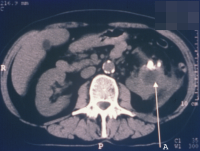

Diagnostisch spielen Sonographie und Computertomographie die entscheidende Rolle: Zumeist fallen die Veränderungen als diffuse Raumforderung auf (Abbildung 20).

Beim Fehlen einer entzündlichen Symptomatik wird differentialdiagnostisch nicht selten sonographisch die Diagnose Tumorverdacht gestellt.

Beispielhaft die bildgebende Diagnostik und das Organpräparat bei einem Patienten mit XGP (Abbildung 21). Hier führte das intraoperative Schnellschnittergebnis Tumor zur Nephrektomie.